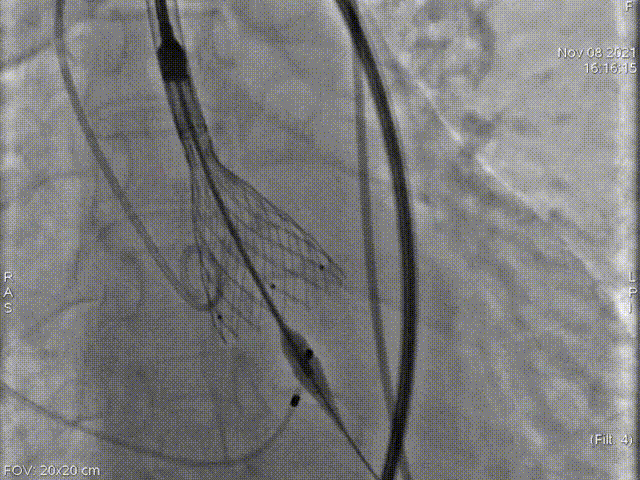

术中影像

主动脉根部造影

术中多次室颤,故当机立断,不进行预扩,直接植入L26号的VenusA-Valve瓣膜。

起始释放

第一次释放

位置稍深,选择回收,重新定位释放

第二次起始释放

第二次释放位置良好

瓣膜打折

球囊后扩

最终位置完美,无瓣周漏